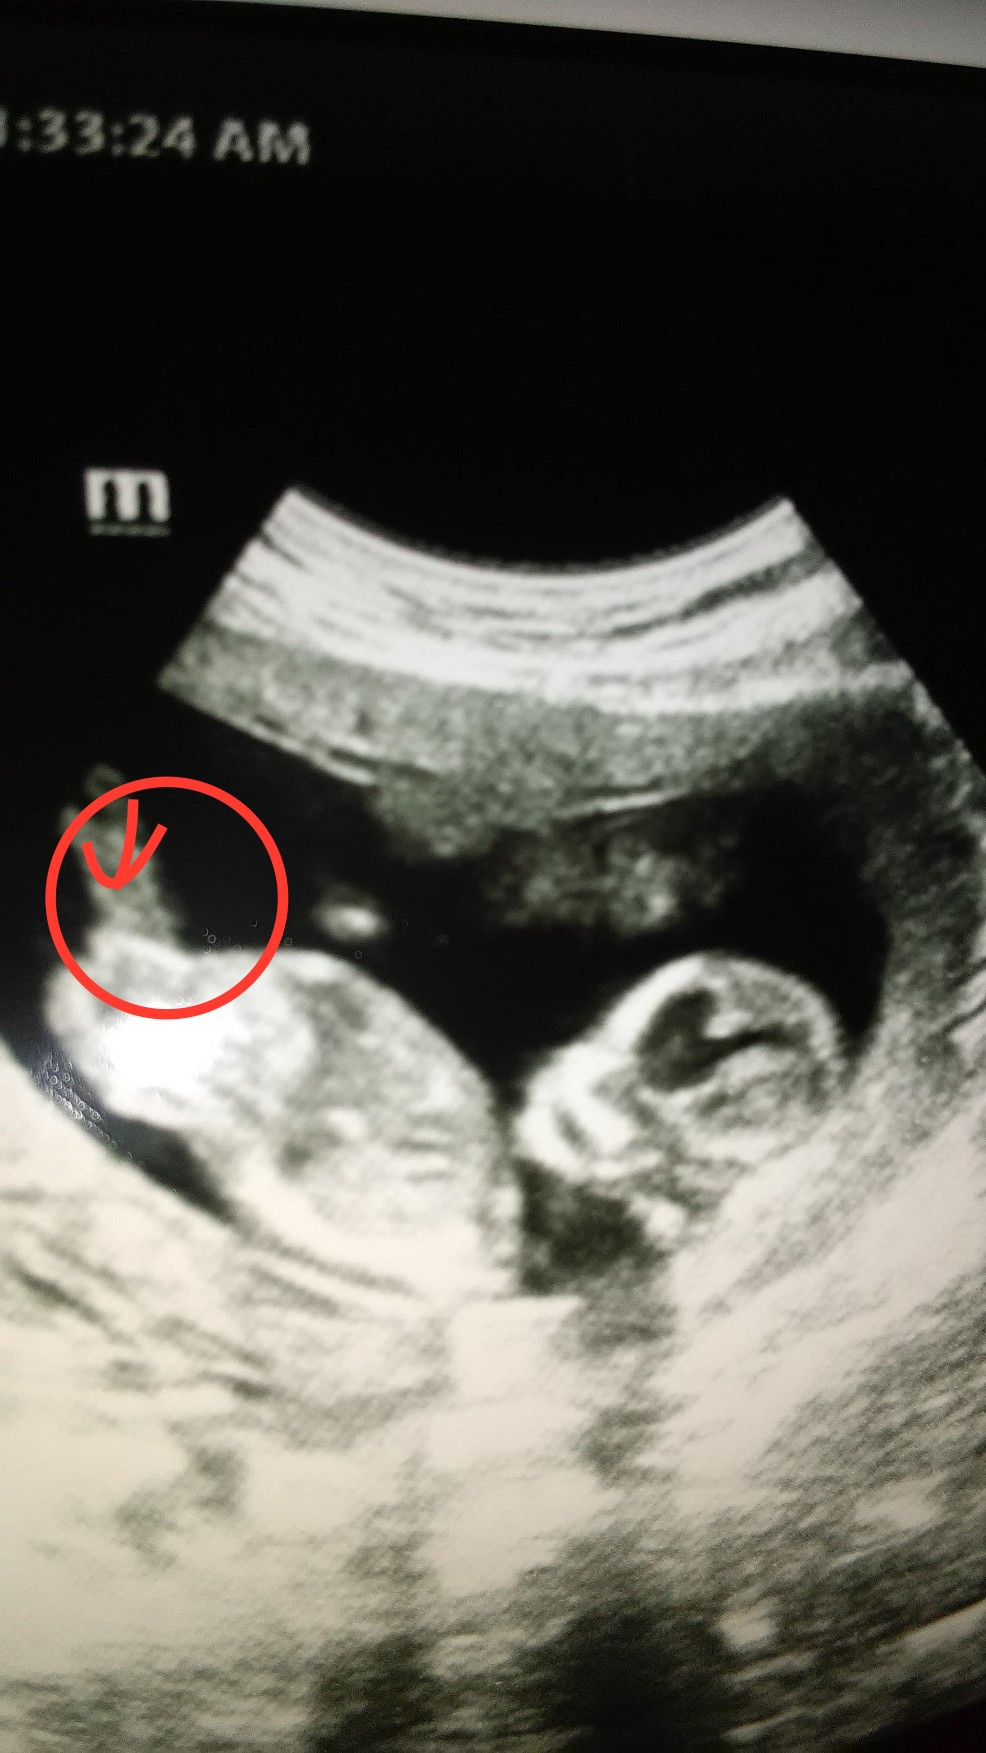

The nub looks long and flat but there is a little bulge at the end. I feel like I can't give an unbiased guess lol

I put at arrow at what I thought was a bulge. I am so excited for her! She doesn't care boy or girl.